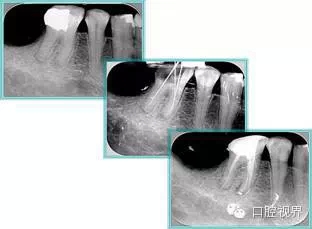

6. 術(shù)后 X 線片

術(shù)后 X 線片用來評定根管充填 長度、致密度(管壁清晰、側(cè)枝)等指標(biāo)。

左圖為根管充填術(shù)后 X 線片。圖中可見,根管充填較好。右下圖有白色小點(diǎn),為側(cè)方加壓導(dǎo)致糊劑擠出所致,表明根管充填比較致密。

致密、恰到好處的充填可去除干凈根管里感染灶,機(jī)體逐漸恢復(fù)。

多根牙時候需進(jìn)行偏移投照,正位投照無法說明具體哪根牙根管充填效果。